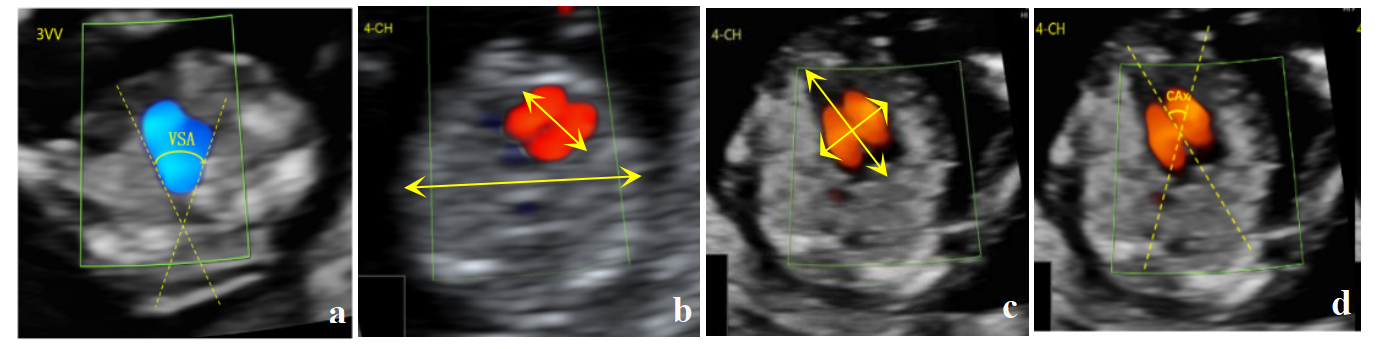

Abstract Body (Do not enter title and authors here): Objective To evaluate the value of combined fetal heart V-angle (VSA), cardiothoracic ratio (CTR), whole heart spherical index (GSI) and axis of the heart (CAx) in predicting congenital heart disease (CHD) in early pregnancy by using color Doppler ultrasonography.

Methods From January 2022 to March 2024, 2529 fetuses with normal fetal heart color Doppler ultrasonography and 50 fetuses with CHD were collected from 11+0 weeks to 16+0 weeks at the double center of Beijing Haidian District Maternal and Child Health Hospital and Fujian Provincial Maternal and Child Health Hospital. The correlation of parameters in early pregnancy and gestational week (GA) was analyzed. The normal reference range and model were established and verified. Based on the established model, the diagnostic efficacy of the four parameters for CHD was quantitatively evaluated and its clinical application value was discussed.

Results There was negative correlation between VSA and GA, positive correlation between CTR and GSI, and no correlation between CAx and GA. Complete the construction of Z-value model of four parameters and the normal reference range of four parameters in five groups of gestational weeks; The establishment of polynomial linear regression model can effectively improve the detection rate of CHD by monomial regression model with single parameter. According to different fetal CHD classification forms, the four parameters have statistical significance in abnormal CHD sites and critical CHD, and can be used as effective parameters for screening CHD in early pregnancy.

Conclusion In this study, the four parameters of CAx, CTR, VSA and CSI can be used as effective parameters for the diagnosis of fetal CHD in early pregnancy. The normal reference range of four parameters in early pregnancy and the combined prediction model of multiple parameters were established for the first time, and the correlation between each parameter and GA in early pregnancy was analyzed to provide quantitative indicators for CHD screening. Further improve the accuracy of CHD early pregnancy prediction.